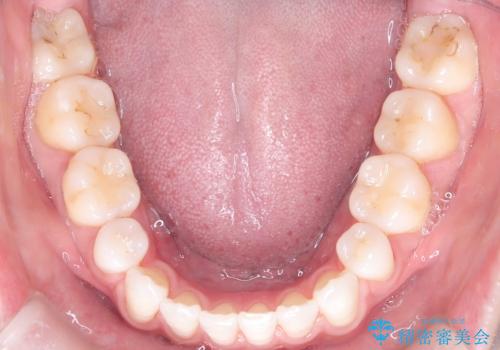

- 患者さんは「口元を引っ込めたい」「八重歯をきれいにしたい」とのご希望で来院されました。診察の結果、上下の前歯が前方に傾斜し、口元がやや突出して見える状態でした。加えて、上顎には八重歯があり、歯列のスペース不足も確認されました。

歯並びと横顔のバランスを整えるためには、前歯を後方に移動させるスペースの確保が必要です。そのため、上下左右の第一小臼歯(合計4本)を抜歯し、ワイヤー矯正で前歯の突出感と叢生(がたつき)を同時に改善する治療計画を立てました。歯を抜くことに抵抗がある方も多いですが、口元の印象を変えるためには非常に効果的な方法です。

上下左右の小臼歯を抜歯後、ワイヤー矯正装置を装着し、全体のバランスを見ながら歯を移動させていきました。特に前歯の後方移動では、抜歯スペースを活かして口元を内側に下げることに重点を置きました。また、八重歯も時間をかけて丁寧に整列させ、左右の正中(真ん中の位置)もぴったりと揃えることができました。

治療期間は約2年で、歯並びだけでなく横顔の印象も大きく改善されました。治療後には「口元がすっきりして笑顔に自信が持てるようになった」とのお声をいただきました。現在は後戻りを防ぐため、保定装置(リテーナー)を使用しながら経過観察中です。ワイヤー矯正は審美性と機能性を両立できる有効な選択肢の一つです。